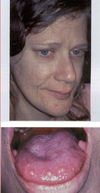

Neurofibromatosis Type 1

Neurofibromatosis